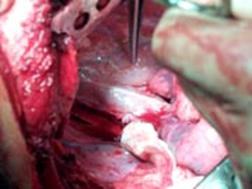

Leziune la nivelul istmului aortic

Aortograma.Leziune

situata distal de Aorta

clampata

emergenta arterei subclavii stangi Segment

lezat excizat